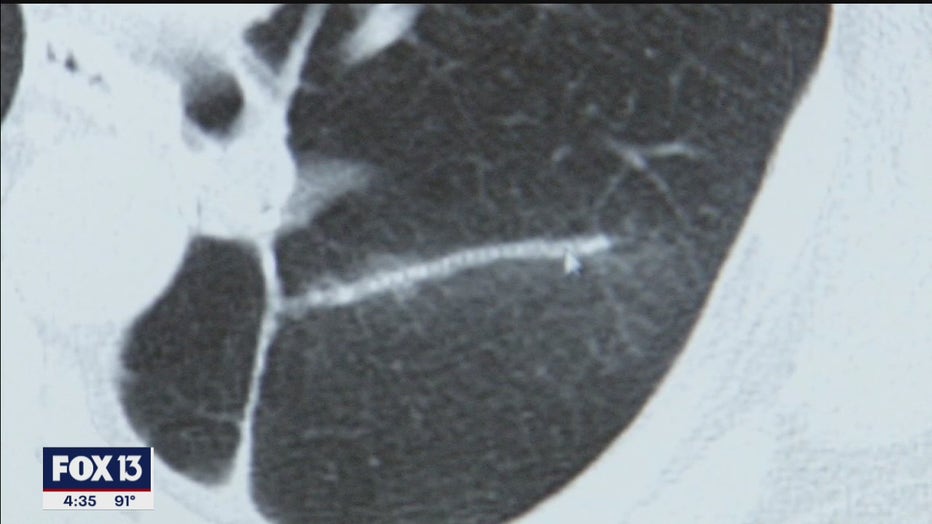

When they found the first spot on her lung, Kathy was 55 and symptom-free.  It was picked on a screening lung CT scan recommended for current and former smokers.

PREVIOUS: CT scan shows lung cancer undetectable by x-ray